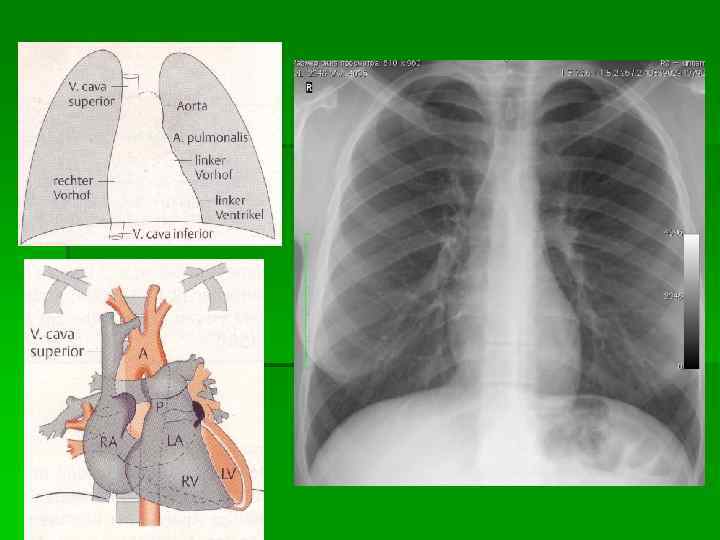

Схема расположения камер сердца и крупных сосудов при контрастном исследовании 1 — трахея, 2 — правый главный бронх, 3 — правый верхнедолевой бронх, 4 — верхняя полая вена, 5 — ортопроекция артерии правого III сегмента, 6 — правая верхнедолевая вена, 7 — нисходящая ветвь правой легочной артерии, 8 — правая базальная вена (из нижней группы легочных вен), 9 — контур диафрагмы справа, 10 — дуга аорты, 11 — ортоградная проекция левой легочной артерии, 12 — артерия III левого легочного сегмента, 13 — левая верхнедолевая вена, 14 — левая нижнедолевая вена, 15 — легочный ствол, 16 — левое предсердие, 17 — левый желудочек, 18 — левый верхнедолевой бронх, 19 — правая легочная артерия, 20 — левый главный бронх.